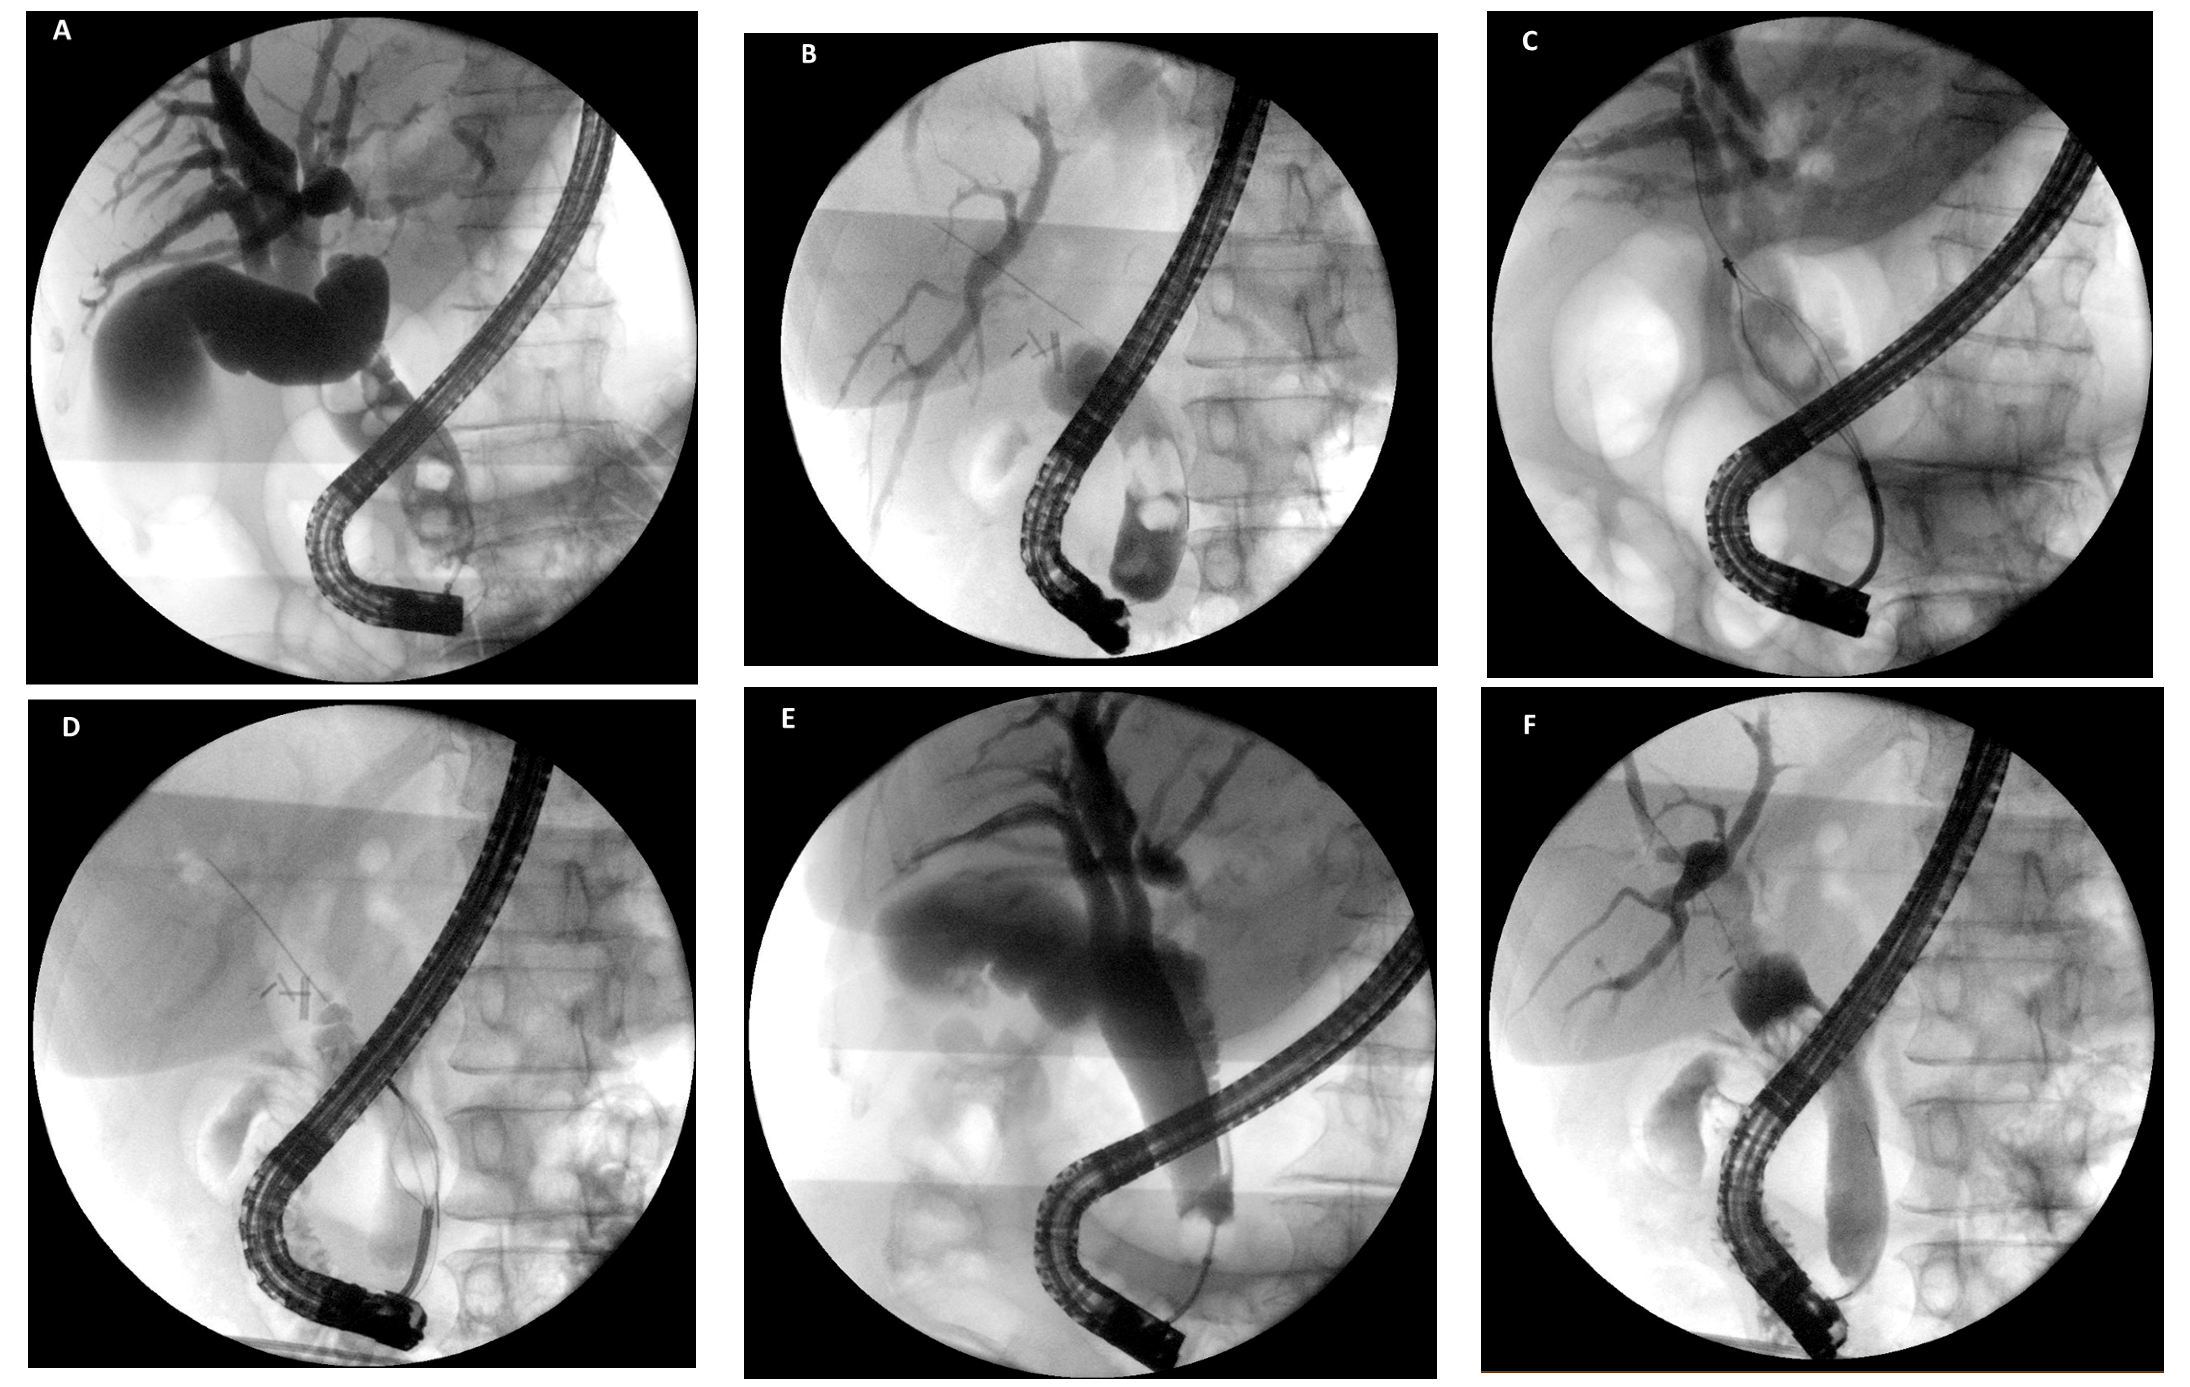

- Bhandari, S.; Bathini, R.; Sharma, A.; Maydeo, A. Usefulness of single-operator cholangioscopy-guided laser lithotripsy in patients with Mirizzi syndrome and cystic duct stones: Experience at a tertiary care center. Gastrointest. Endosc. 2016, 84, 56–61. [Google Scholar] [CrossRef] [PubMed]

- Chon, H.K.; Park, C.; Kim, T.H. Minimally Invasive Approach Using Digital Single-Operator Peroral Cholangioscopy-Guided Electrohydraulic Lithotripsy and Endoscopic Nasogallbladder Drainage for the Management of HighGrade Mirizzi Syndrome. Clin. Endosc. 2021, 54, 930–934. [Google Scholar] [CrossRef]

- Binmoeller, K.F.; Thonke, F.; Soehendra, N. Endoscopic treatment of Mirizzi’s syndrome. Gastrointest. Endosc. 1993, 39, 532–536. [Google Scholar] [CrossRef]